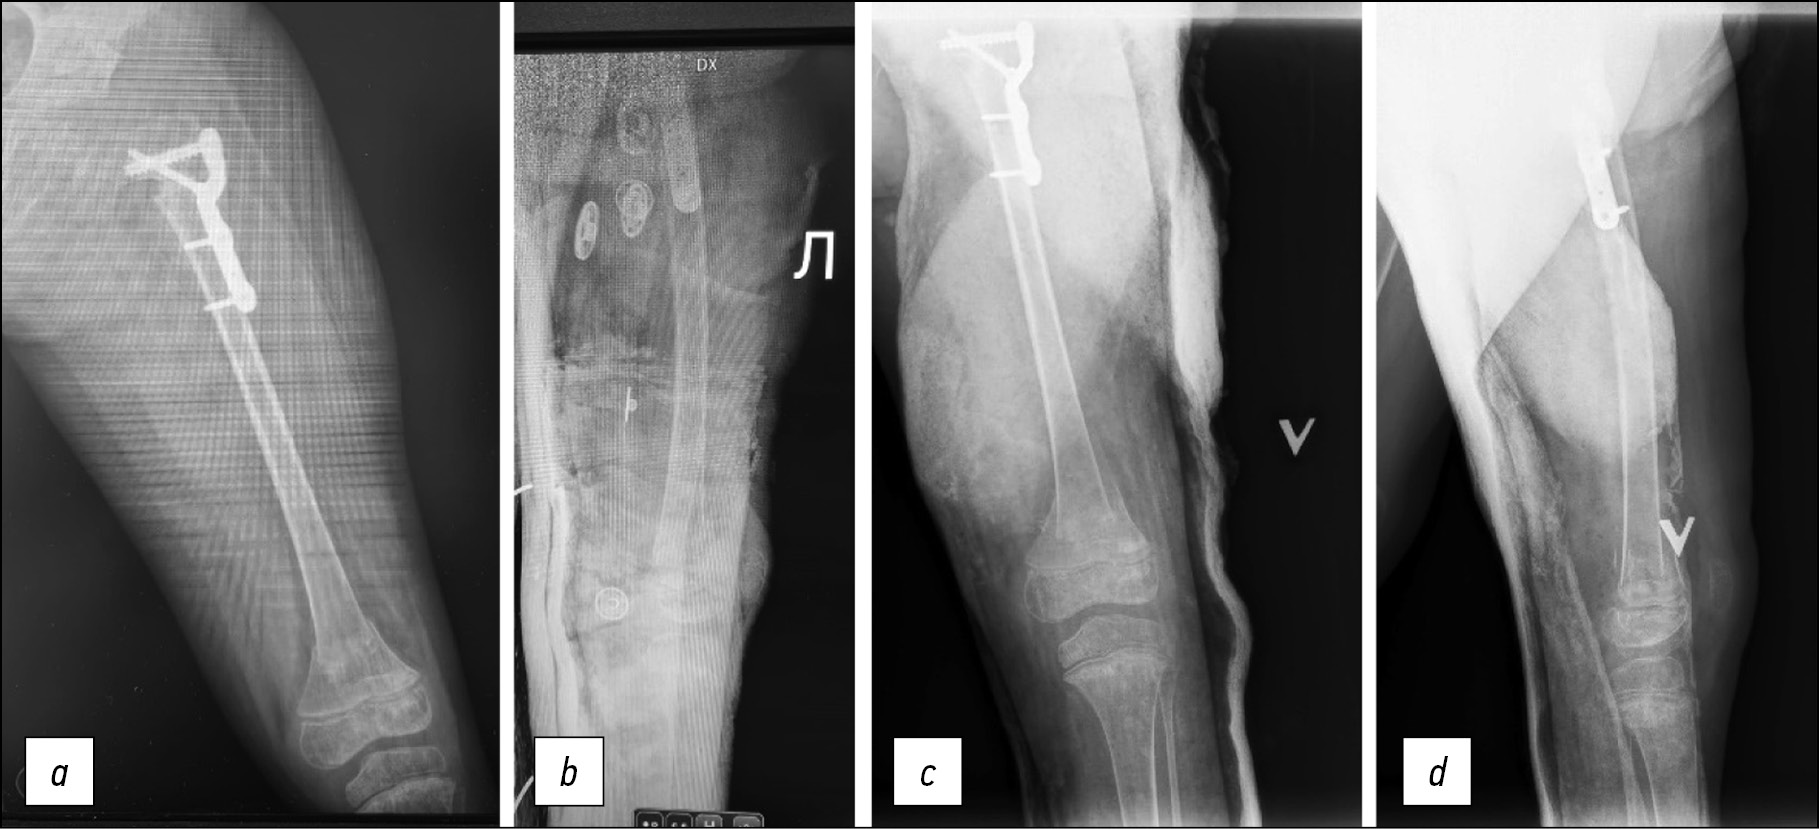

Ребёнок, 10 лет, ДЦП, IV уровень по GMFCS. Ремиссия эпилепсии длительностью 3,5 года, продолжает принимать противоэпилептические препараты. Перелом произошёл во время ЛФК. На рентгенограмме косой винтообразный перелом диафиза бедренной кости со смещением. Первичная попытка лечения путём закрытой репозиции и гипсовой иммобилизации. На контрольной рентгенограмме выраженное смещение отломков. В процессе хирургического лечения репозиция отломков не удавалась из-за выраженной ретракции подвздошно-поясничной мышцы и длинной приводящей. Выполнено хирургическое лечение: тенотомия подвздошно-поясничной мышцы справа и удлинение сгибателей коленного сустава для правильного позиционирования ребёнка, коррекции сгибательной контрактуры коленного сустава и одномоментное устранение смещения, металлоостеосинтез эластичными тенами. На контрольной рентгенограмме положение отломков удовлетворительное. Через 12 месяцев полная консолидация в зоне перелома (рис. 2).

Рис. 2. Пример лечения винтообразного диафизарного перелома у пациента 10 лет, рентгенограммы: a — перелом с выраженным смещением; b — иммобилизация гипсовой повязкой, отсутствие коррекции смещения; c — выполнение интрамедуллярного эластичного армирования; d — через 12 месяцев после операции

Fig. 2. An example of treatment of a helical diaphyseal fracture in a 10-year-old patient, radiographs: a — fracture with pronounced displacement; b — immobilization with a plaster cast, no correction of displacement; c — performing intramedullary elastic reinforcement; d — 12 months after surgery